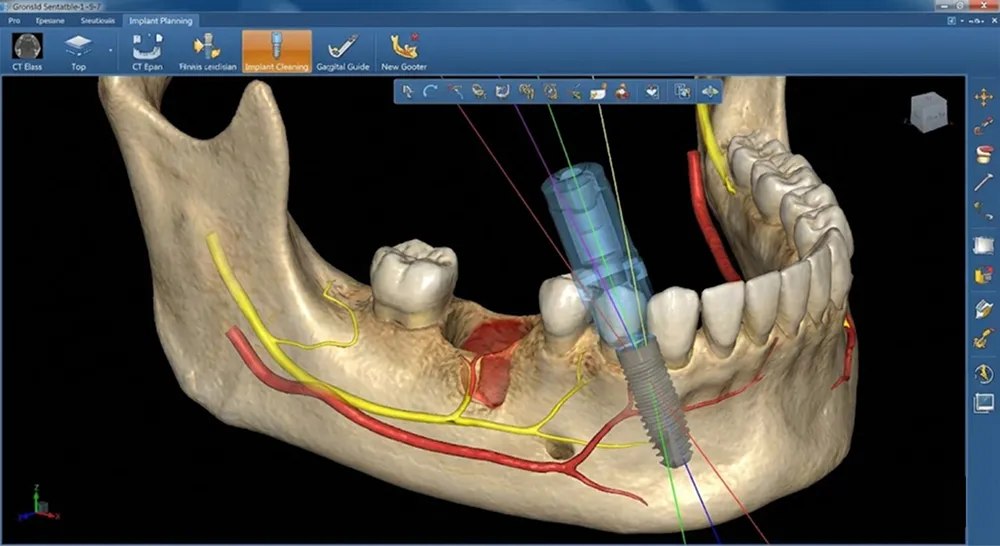

理由3 専用手術室・最新歯科CTなど、安全な治療を支える充実の設備

インプラント治療の安全性は、設備環境にも大きく左右されます。当院では以下の設備を完備し、より安全な治療環境を整えています。

歯科用CT

従来のレントゲンでは把握できなかった骨の厚さ、神経・血管の位置を3次元的に確認できます。最小限の被曝で精密な検査が可能です。

シミュレーションソフト

CT画像をもとに、埋入位置・角度・深さを事前にシミュレーションします。これにより、手術計画をより具体的に立てることができます。

サージカルガイド

シミュレーション結果を反映したマウスピース型の装置です。計画に沿った位置への埋入をサポートします。

当院のインプラント治療の特徴

インプラント治療を成功させるために大切なことは、術前に精密な情報(データ)を取得し、正確な治療計画を実行することです。

当院では「経験や勘」に頼るのではなく、精密機器を活用した「データ」に基づいた安全なオペ体制を整えています。

特徴① 人為的なミスを減らすことを目指した「3Dコンピューターインプラント」

当院では、高解像度CTとシミュレーションソフトを活用した「3Dコンピューターインプラント」を導入しています。

CT画像から神経や血管の位置を3次元的に把握し、コンピューター上で理想的な埋入位置・角度・深さを計画。その計画をもとに「サージカルガイド」というマウスピース型の装置を作製します。

手術時にはこのガイドを使用することで、計画通りの位置に精密にインプラントを埋入することができます。これにより、人為的な誤差を減らし、安全性と精度に配慮した治療を心がけています。